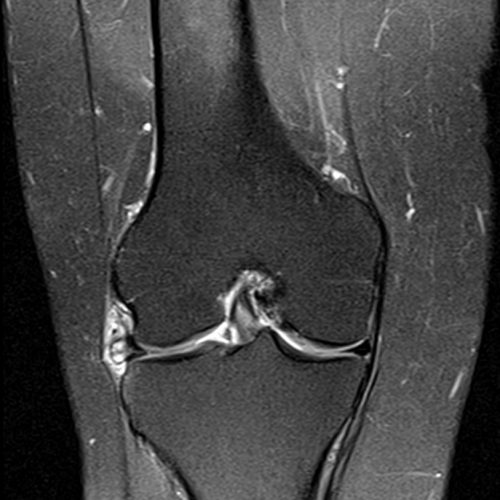

Lesão horizontal do menisco lateral e cisto parameniscal.

Corredora com dores na região do compartimento lateral do joelho e sensação de aumento de volume com formação de um nódulo palpável.

Realizado exame de ressonância magnética com identificação de lesão horizontal do menisco lateral (seta pequena) e formação cística parameniscal.